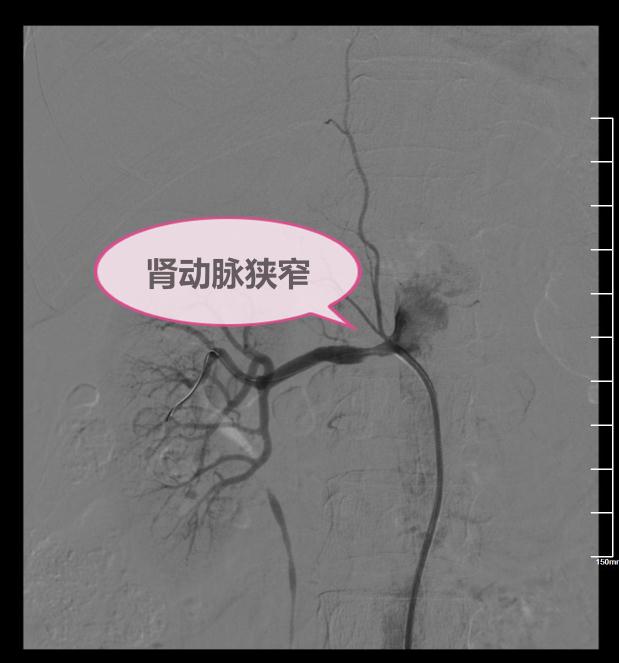

陈大叔今年55岁了,血压已经高了四年了,平时都一直浮动在180/100mmgh左右,服用各种降压药就是控制不下来,还出现了血尿、腰背部隐痛。身体的不适让陈大叔焦虑不安,如此恶性循环导致血压也是越来越高,被疾病折磨的陈大叔也是四处就诊,后听人介绍来到四川省林业中心医院,找到了内四科的肖红主任,医生了解病情后立即做了一个彩超:原来是肾动脉狭窄引起的一系列并发症。

什么是肾动脉狭窄呢?顾名思义,就是肾动脉变窄了,堵车了,血流不畅通了,引发了持续性的高血压,药物无法控制。

治疗方法:常用球囊扩张肾动脉后放置血管支架

肖主任向陈大叔介绍了科室特色:微创介入治疗即在DSA引导下右肾动脉球囊扩张及支架植入术。此技术创口小,费用低,无副作用,不会对患者身体造成伤害。